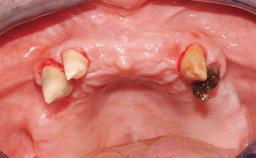

ITI Curriculum FL: Patient Assessment Case 10

Example intended for case-based discussion regarding patient assessment, diagnosis and determination of risk and complexity.

| Case Type | Short Space |

| Jaw | Maxilla and Mandible |

| Area | Posterior |

| # of Teeth | 3 |

Surgical SAC classification

| Placement Protocol | - |

| Tooth Site | - |

| Socket Morphology | - |

| Socket Integrity | - |

| Bone Volume | - |